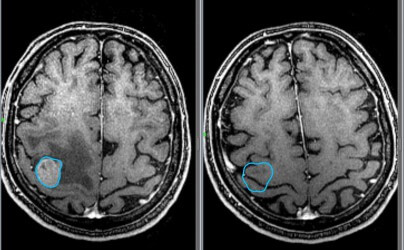

- МРТ с введением контрастного вещества;